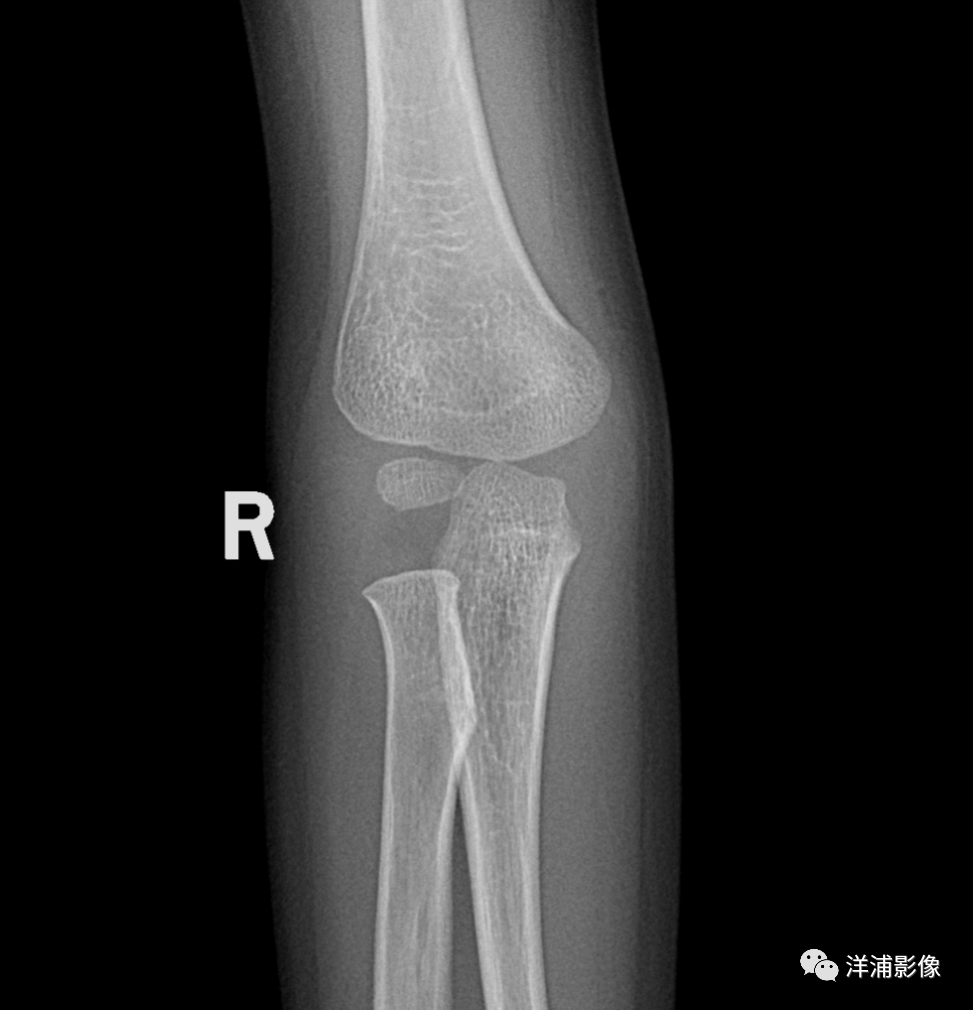

男,4岁,右肘外伤:

脂肪垫通常可在X线平片上显示,但当急性创伤导致软组织肿胀和出血时,脂肪垫可能移位或显示不清。在已知的众多脂肪垫中,目前最有意义的是肘关节囊内脂肪垫和膝关节髌上脂肪垫。当肘后脂肪垫及帆状前脂肪垫显现时,可诊断此为肘关节积液。肘后脂肪垫的显示强烈提示关节囊内隐匿性骨折,但1/4的患者在随访中无阳性发现。

脂肪垫征(fat pad sign):又称帆船征(Sailing sign) 或八字征;细微的软组织表现是骨折的标志,不应漏掉。前后脂肪垫移位提示肘关节内的积血、积液改变,使关节滑膜、脂肪垫被推移,在侧位片上呈“船帆”状;虽然有时肘关节X片中看不到骨折线,但是出现前脂肪垫征时强烈提示有桡骨小头骨折。

脂肪垫征≠骨折,只是说骨折的概率明显增大。

部分研究表明前脂肪垫征(anterior fat pad sign)发生关节内骨折的概率为70-80%。后脂肪垫征(posterior fat pad sign)发生关节内骨折的概率达90%。